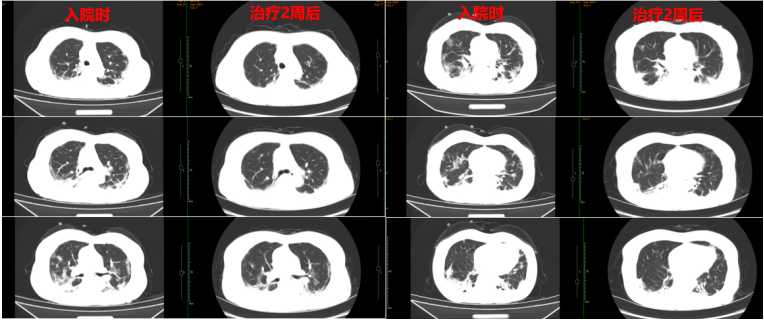

复查胸部CT可见病灶明显吸收(图8)

图片

图8  患者治疗前后胸部CT比较